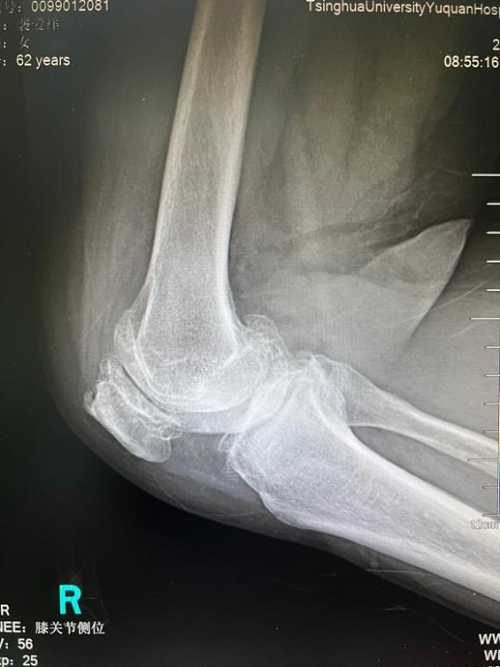

在我院骨科病区,62岁的袭奶奶就享受到了新政策带来的实惠。袭奶奶一直饱受膝关节炎的折磨,膝关节反复疼痛,行走十分困难。她接受了长期的保守治疗,但疗效很差,所以人工膝关节置换是她最后的救命稻草。但苦于人工膝关节价格昂贵,一直没有下定决心接受手术。

袭奶奶一听说人工关节大幅降价后,第一时间就找到骨科贾育松主任,接受了人工全膝关节置换手术。手术效果很好,恢复很快,第二天就在助行器的辅助下站立活动。出院两周后来门诊复查时,走路已完全不需要任何辅助,她表示对治疗效果非常满意,还说赶上了国家的好政策,既治好了病,也节省了治疗费用。